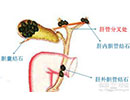

急性梗阻性化脓性胆管炎

疾病介绍:急性梗阻性化脓性胆管炎泛指由阻塞引起的急性化脓性胆道感染,是胆道外科病人死亡的最重要、最直接的原因,多数继发于胆管结石和胆道蛔虫症。发病基础…【详细】